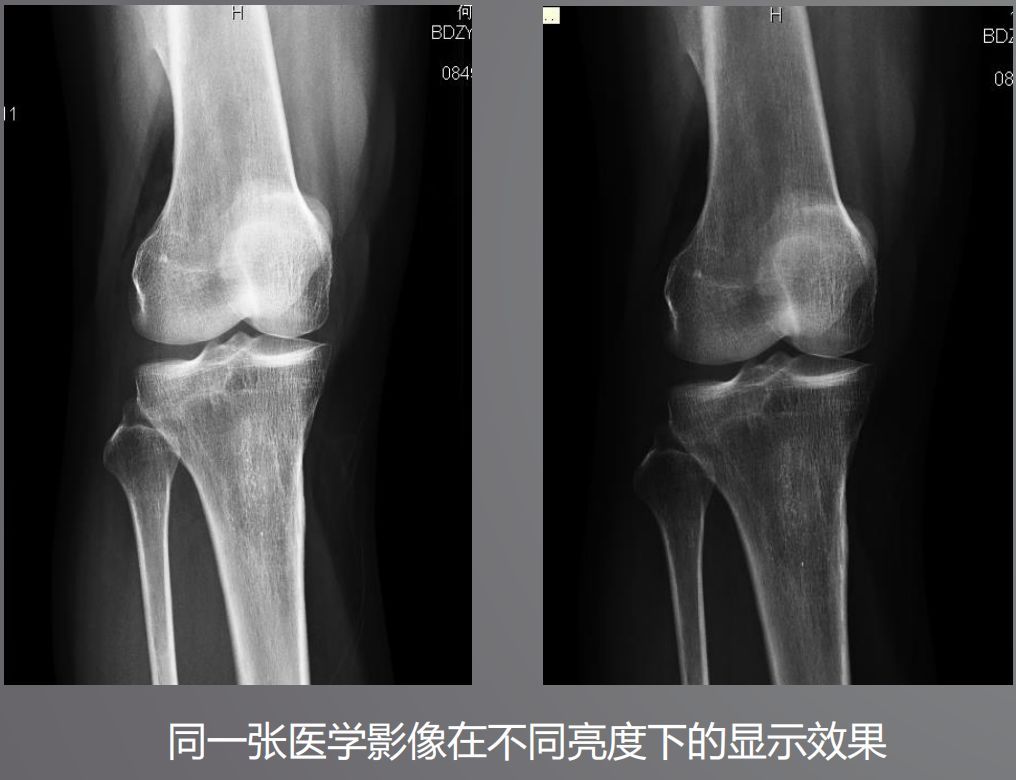

三、高亮度

高亮度从字面上就非常好理解了,回想在传统胶片时代,阅片都是直接夹在大大的发光白板上。而平时我们浏览网页或者看视频并不需要那么高的亮度,导致普通显示器亮度偏低,达不到医用阅片的标准。

根据DICOM Part14规定,所有医学显示器必须符合GSDF的标准,确保显示区域亮度符合一致性。而普通显示器是不需要刻意符合这个标准的。

医用显示器通过系统测量和调整每一个像素的亮度,降低中心和角落之间亮度和色彩的不均匀性,通过减少这些差异,确保显示器每个显示区都能符合DICOM GSDF标准。